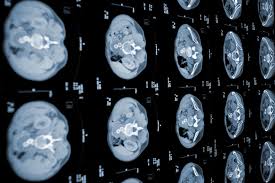

Pancreatic Cancer Symptoms Causes Types Stages And Treatment from www.drugwatch.com I'm so sorry to have to say that. The pancreas also produces insulin which aids in the metabolism of sugar in the cat's body; The exact cause of pancreatic cancer in cats is not yet clear. Ultrasound examination by an experienced veterinarian can identify changes to the pancreas in up to ⅔ of cats with pancreatitis, including pancreatic inflammation, inflammation of surrounding tissue, pancreatic enlargement, or fluid surrounding the area. When a cat has this type of cancer, he will only survive a couple of months, because symptoms don't usually appear until the cancer is in its later stages. But not all is lost. This technology involves several sets of ct scans taken over several minutes. However, when it does occur, it is deadly.

This technology involves several sets of ct scans taken over several minutes.

There is still much that we don't know about pancreatitis in cats, but thankfully, the veterinary community's knowledge base has grown over the years, so there are things we can do to help prevent and treat this disease. Pancreatic cancer is more common in older cats, suggesting that it may be associated with age, or a combination of risk factors. Cats with pancreatic cancer rarely survive more than a few months after the time of diagnosis. Altogether, the most common pancreatic cancer in dogs and cats are insulinomas, followed by adenocarcinomas. of the endocrine tumors, there are 3 types: Also known as pancreatic protocol ct, this helps identify staging and whether or not surgery would be an effective option. This technology involves several sets of ct scans taken over several minutes. Just as cats have the same anatomy we do and can get the same types of cancers we do, the treatment of cancer in cats is almost identical to the treatment of cancer in people. • intraductal papillary mucinous neoplasm. The exact cause of pancreatic cancer in cats is not understood at this time. But not all is lost. Some of the other risk factors for pancreatic cancer include smoking, chronic pancreatitis (inflammation of the pancreas), family history of pancreatic cancer, obesity and certain genetic syndromes. Pancreatitis (inflammation of the pancreas) is a gastrointestinal disorder that can affect cats. Insulinoma in cats insulinomas are malignant neoplasms — fast growing cancerous tissue — of the beta cells in the pancreas.